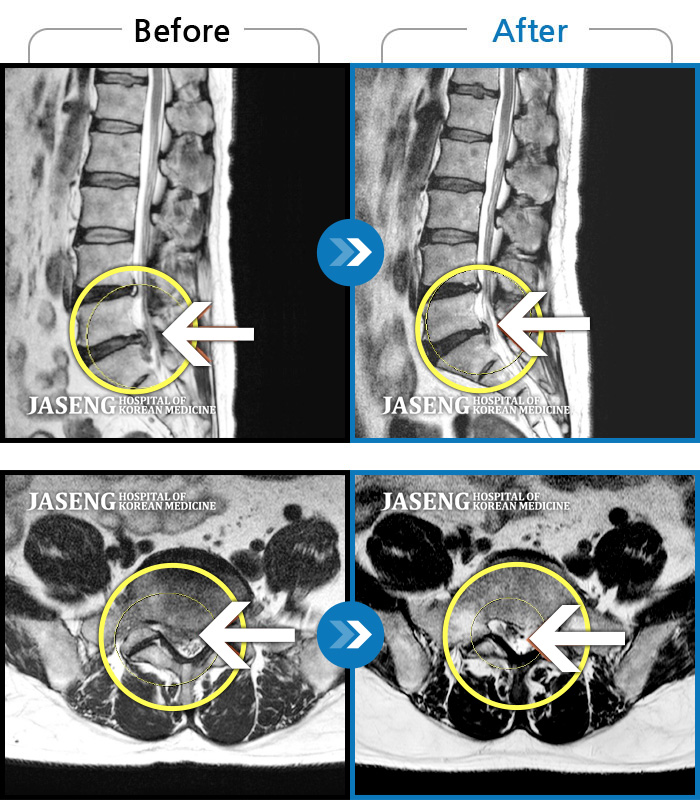

허리통증이 급속도로 좋아지는걸 경험하면서 신기하리만큼 지금 현재는,,

특히 본인의 "허리통증"만큼은 통증지수가 지금 현재는 "0" 이라고 자신있게 말씀드릴수 있습니다^^

며칠전에 양반다리를 자연스레 하게됬는데요,, 참고로 최희승 원장님 만나뵙기전에는 본인이 양반다리를 한다는건 상상도 할수없는 일이었답니다 ^^

아마 허리 병 앓아보셨던,현재 앓고 계시는 환자분들은 아실꺼에요.. 허리디스크 통증이 있을때는 양반다리를 한다는게 절대 쉽지가 않거든요 ^^~~

저도 놀랄정도로 양반다리를 일부러 오래 하고 앉아있어 보았는데요,, 정말 아무렇지도 않길래 너무 기분이 좋았지 뭐에요 ^^